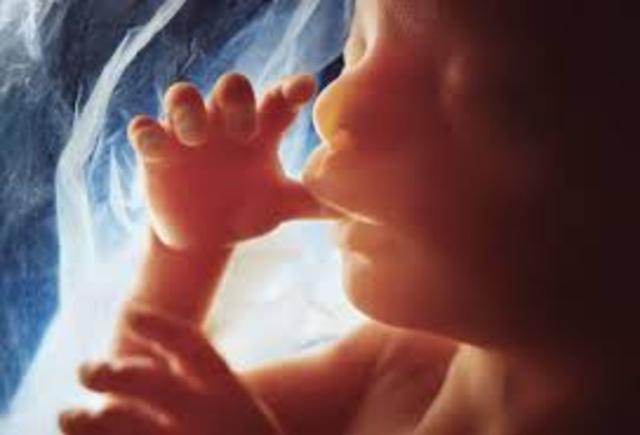

• Baby can see

Baby can see

The baby becomes sensitive to light around the twenty fifth week of pregnancy.

• Baby becomes sensitive to touch

Baby becomes sensitive to touch

Fetus becomes sensitive to touch around 32 weeks. He can feel now a single hair stroke.